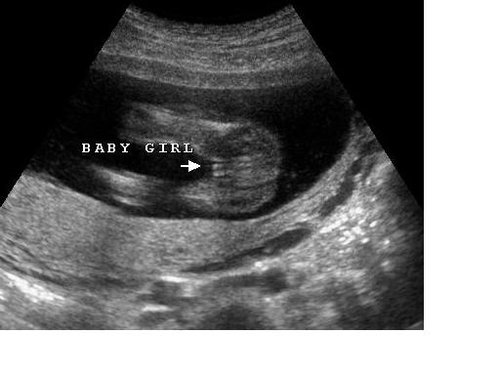

@nicolettka2126 tak to je super,ze je vsetko v poriadku..a to asi rovila v 3D,ze? Vies co hovorila,ze z jedneho profilu sa jej aj zda,z druheho,ze nie je vidno nic..a ze semenniky este nevidi ,tak to moze byt aj pipocnikova snura..,tak vydrzim este 3 tyzdne a uvidime 🙂 a ja podla toho co mi ukazovalo by som teda neidentifikovala pohlavie urcite 🙂

@melisssssa nie nie praveze obycajne sono mi robila vob3c ani na chvilu neprepla do 3D 🙂 Mojej dr sa podarilo taky uhol spravit s tym strojom na mojom brusku ze som mala kraaasny pohlad zospodu na obe nozicky a pisulinku 🙂 Drzim teda velmi silno palceky aby si nabuduce uz aj ty vedela 🙂

@nicolettka2126 tak pisulka teda 😁super💝💝💝💝💝💝💝💝

@melisssssa podla mna na sono je vidiet zrnko,ked to je baba,pupocnik nepupocnik. Nasa mala zrno ukazkove,aj ja som to rozpoznala.. Tak nechapem,preco ti to nepozrela poriadne ☹ ale nabuduce uz snad bude vidiet 😉 kedy mas dalsi termin?

@melisssssa toto je foto z netu,ale takto podobne vyzerala nasa pisulka 🙂 hned som to spoznala,ze to tam nic nestoji a nehompala,ale je tam zrnko 😀